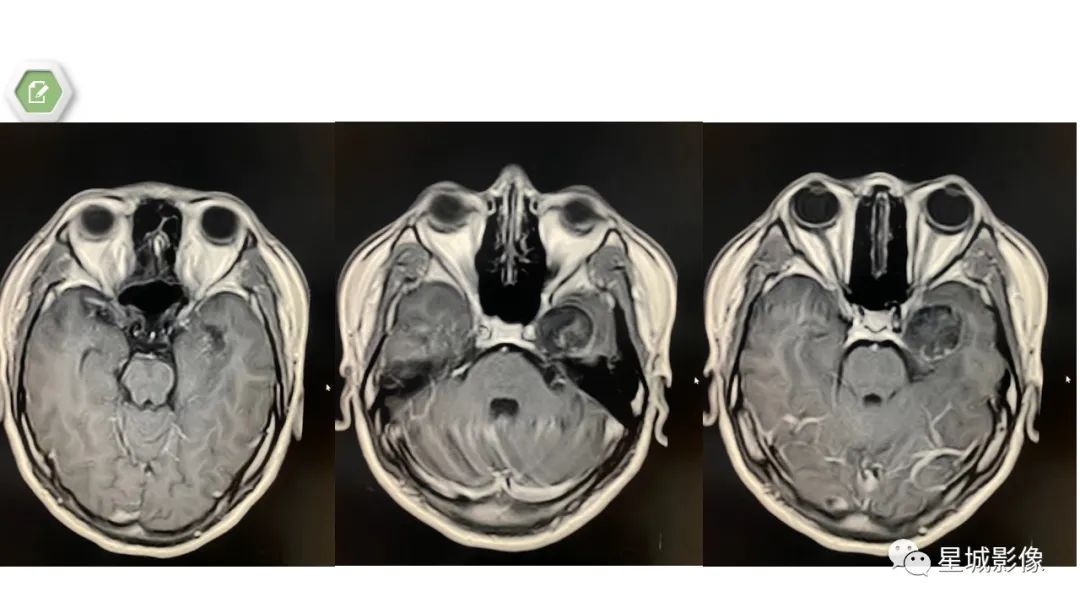

颅内成熟性囊性畸胎瘤1例MR影像表现

【病例】颅内成熟性囊性畸胎瘤1例MR影像表现-1

【病例】颅内成熟性囊性畸胎瘤1例MR影像表现-2

【病例】颅内成熟性囊性畸胎瘤1例MR影像表现-3